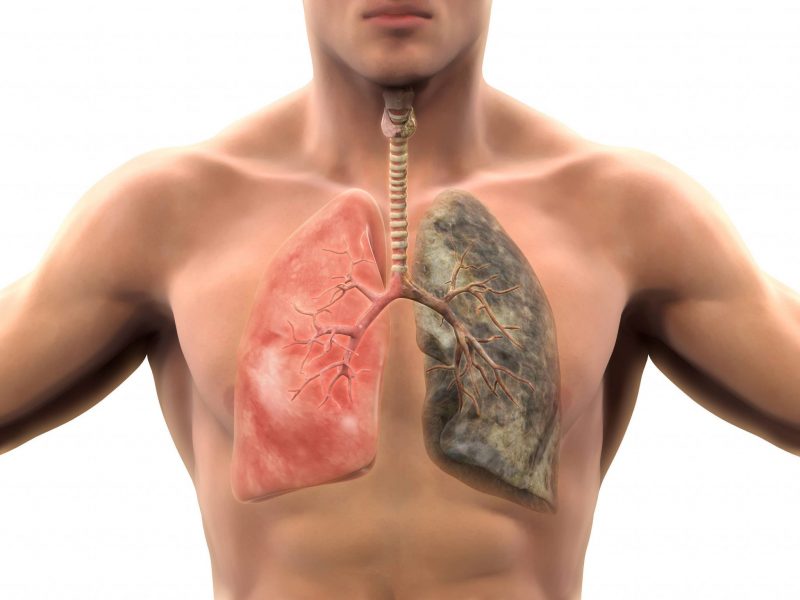

При общении с пациентом врач обычно узнает, что перед ним человек с большим стажем курения (более 10 лет), у которого часто бывают простуды, инфекционные заболевания дыхательных путей и органов дыхания.

При приеме врач проводит количественную оценку курения (пачки/лет) или индекс курящего человека (индекс 160 – риск развития ХОБЛ, выше 200 – «злостный курильщик»).

Избавление от бронхита у курильщика возможно лишь при условии, что пациент откажется от вредной привычки.

Отказ от курения является основным условием, которое, если выполнено, может по крайней мере уменьшить проявление симптомов заболевания.

- Избавление от вредной привычки курения, что значительно повышает вероятность успешного лечения.

Сначала нужно избавиться от всех раздражителей, которые способствуют развитию заболевания: необходимо прекратить курение, стремиться к здоровому образу жизни и проводить больше времени на свежем воздухе. Если причиной является опасная работа, вызывающая сужение и спазмы бронхов, то лучше всего ее сменить.